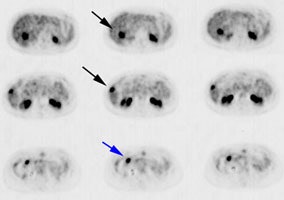

Initial staging for extrahepatic metastases: The patient below underwent FDG PET imaging to assess for extrahepatic metastatic disease prior to definitive surgical intervention. The PET exam demonstrates uptake within two hepatic metastases (black arrows on PET scan and yellow arrows on CT images) and in the patients primary colon cancer (blue arrow on PET scan and white arrow on CT image). No other sites of abnormal tracer uptake were identified which supports surgical intervention in this case. |